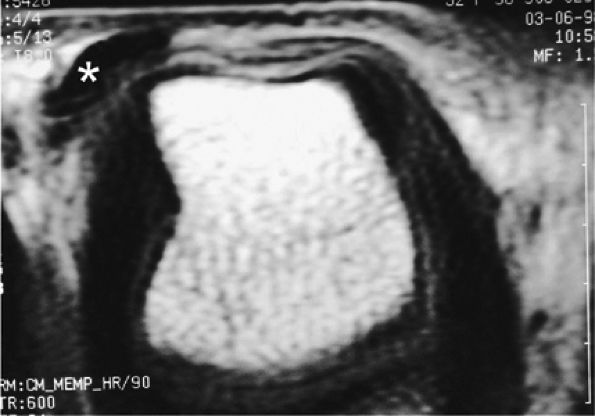

The T1-weighted spin-echo sequence clearly delineates the major structures of interest within the distal interphalangeal (DIP) joint.3

-

Fat suppression is necessary for T2-weighted images because of the large amount of fat in the subcutaneous tissue of the fingers.